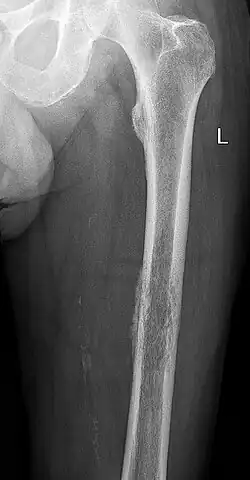

- 3 – Der Tumor wächst rasant und destruierend ohne Respektierung anatomischer Grenzen ("permeativ"), reaktive Sklerosierungen sind eine große Ausnahme. Die Begrenzung ist meist nicht mehr erkennbar, und die Periostreaktion ist "Zwiebelschalen-artig", teils unterbrochen, an den Rändern der Periostabhebung können sich Codman-Dreiecke ausbilden. Im benachbarten Weichgewebe können durch die Weichgewebs-Ausdehnung des Tumors Spiculae sichtbar sein. Typische Vertreter sind die hochmalignen Osteosarkome und Ewing-Sarkome.

Die Einteilung stammt aus der Zeit vor Einführung von Computertomographie und Magnetresonanztomographie und hat durch diese Verfahren an Stellenwert verloren. Sie kann überdies nur bei solitären, fokalen Knochenveränderungen angewandt werden, nicht jedoch bei generalisierten Knochenveränderungen und nur eingeschränkt bei Knochenmetastasen. Trotzdem ist sie gut zur Beschreibung des nativradiologischen Befundes geeignet, da allein aufgrund der Röntgenmorphologie Aussagen zur Aggressivität des Tumors möglich sind. Andererseits berücksichtigt sie nicht die Lokalisation des Tumors im Knochen, ob metaphysär, diaphysär oder epiphysär, ob spongiös, kortikal oder gemischt, ob zentral oder randständig.

Hintergrund der Einteilung ist, dass bei langsam oder nicht wachsenden Knochentumoren, wie bei einer Knochenzyste, der Tumorrand in der Regel klar abgegrenzt ist und eine reaktive Umgebungsreaktion in Form einer Sklerosierung, Osteosklerose oder Knochenneubildung stattfindet, um den mechanischen Verlust, der durch die weniger stabile Zyste entsteht, mechanisch auszugleichen. Hingegen wachsen aggressive Tumoren, wie das Osteosarkom, derart schnell, dass sie den Knochen diffus ohne erkennbaren Rand zerstören und keine Zeit für reaktive Umbauvorgänge bleibt. Ebenso reagiert das Periost, wenn es durch ein Tumorwachstum vom Knochen abgehoben wird, mit einer Knochenneubildung, sodass bei schnellem Wachstum schalenförmige Neubildungsstreifen ("Zwiebelschalen") zu erkennen sind, während gutartige Tumoren gar nicht bis zum Periost vordringen bzw. keine Periostabhebung hervorrufen.